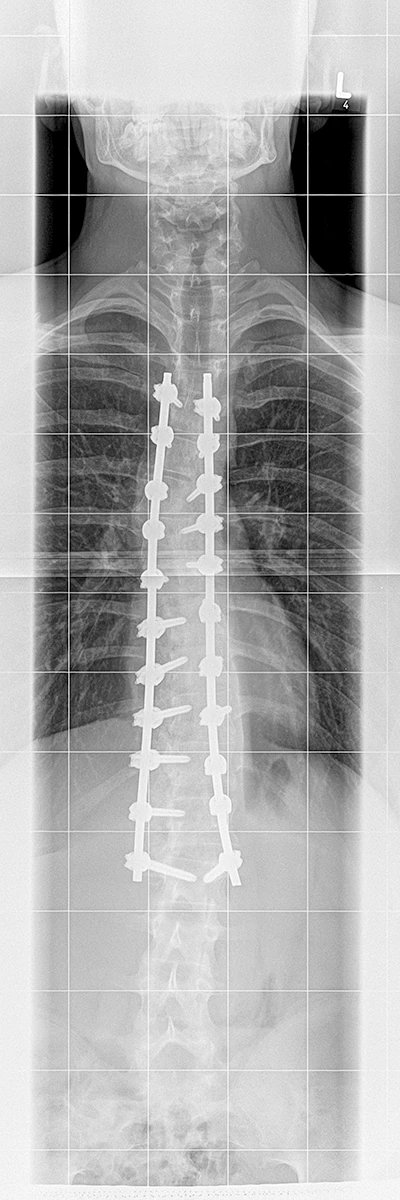

Röntgenbild Post-OP

Die Operation fand am 30.6.2025 statt und dauerte letztendlich 9 Stunden.

Der Cobb-Winkel konnte insgesamt auf unter 15 Grad verbessert werden! Damit hatte niemand gerechnet und wir sind alle sehr glücklich darüber.

Ich habe die OP sehr gut weggesteckt. Die intensivmedizinische Betreuung in den Tagen danach war hervorragend. Nach 3 Tagen konnte ich mit Unterstützung der Physiotherapeutin mit einer Gehhilfe aufstehen und erste Schritte machen. Bereits am 6. Tag nach der OP wurde ich nachhause entlassen.